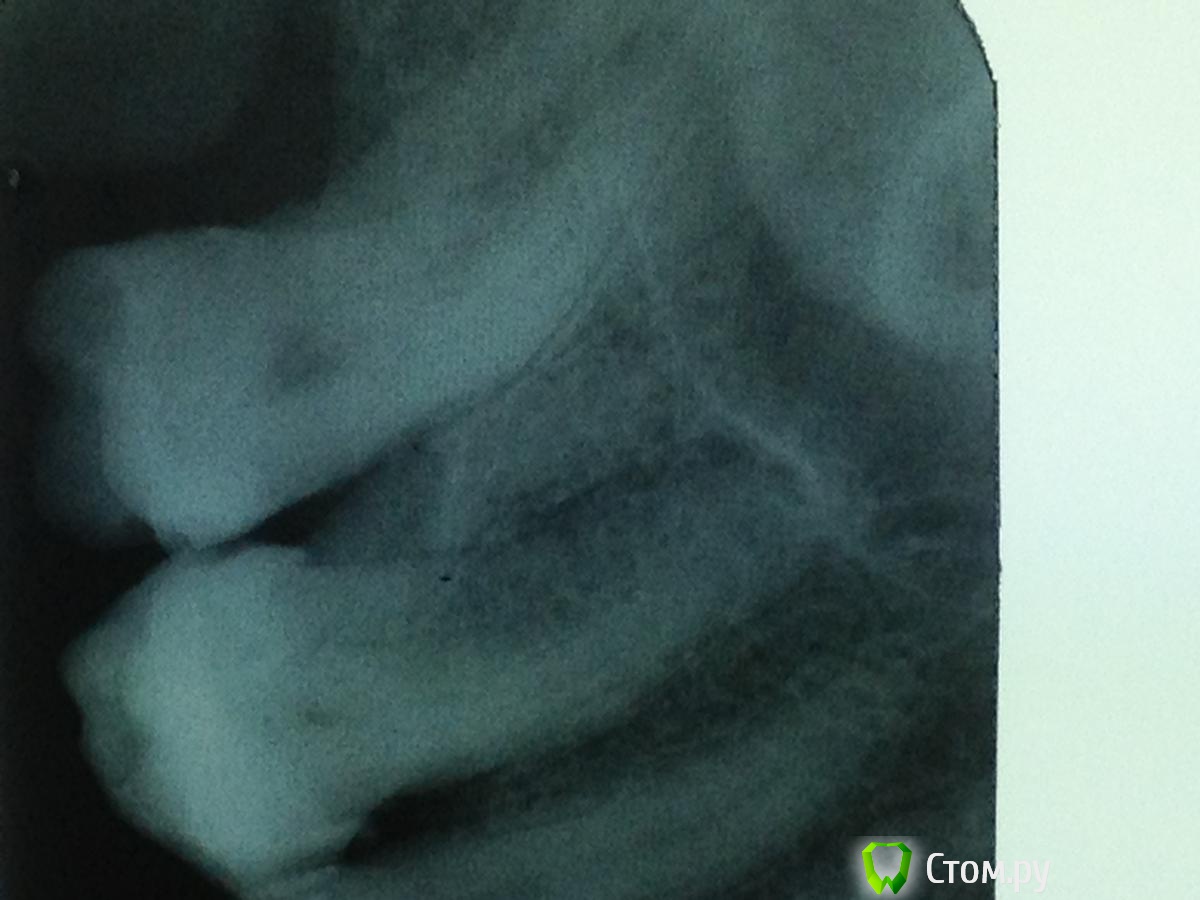

Solnyshko Опубликовано 8 марта, 2014 Поделиться Опубликовано 8 марта, 2014 26 зуб . Пациента беспокоит дискомфорт и отечность слизистой в этой области. Перкуссия безболезненная . Между 26 и 27 зондируется глубокий костный карман. Прошу совета - зуб подлежит удалению? Что вы видите на снимке резорбцию корня или это костный карман? Ссылка на комментарий

Каплан Опубликовано 8 марта, 2014 Поделиться Опубликовано 8 марта, 2014 Снимок не четкий. убрать пломбу, прокрасить дно на предмет трещины. (если карман одиночный, то первое на что наталкивает - трещина)вариантов не так много. 1- трещина2-кариес убежавший в корень3- инвазивная цервикальная резорбция. все три вариант грозят удалением. но даже если и так, я бы ради спортивного интереса убрал пломбу и посмтотрел что там... Ссылка на комментарий

Solnyshko Опубликовано 8 марта, 2014 Автор Поделиться Опубликовано 8 марта, 2014 Снимок не четкий. убрать пломбу, прокрасить дно на предмет трещины. (если карман одиночный, то первое на что наталкивает - трещина)вариантов не так много. 1- трещина2-кариес убежавший в корень3- инвазивная цервикальная резорбция. все три вариант грозят удалением. но даже если и так, я бы ради спортивного интереса убрал пломбу и посмтотрел что там... Вот,наверное третий вариант.На КТ нет смысла гонять человека? Ссылка на комментарий

Гарриевич Опубликовано 10 марта, 2014 Поделиться Опубликовано 10 марта, 2014 По снимку я бы сказал, что это кариес корня 26. Уберете пломбу, скорее всего провалитесь в кариозную полость.Как уберете пломбу рассажите чО там было Ссылка на комментарий

Seryogin Опубликовано 11 марта, 2014 Поделиться Опубликовано 11 марта, 2014 По снимку я бы сказал, что это кариес корня 26. тоже первая мысль при виде снимка. но если приглядеться, то там убыль костной ткани. поэтому участок корня выше уровня кости кажется менее контрастным.) Ссылка на комментарий